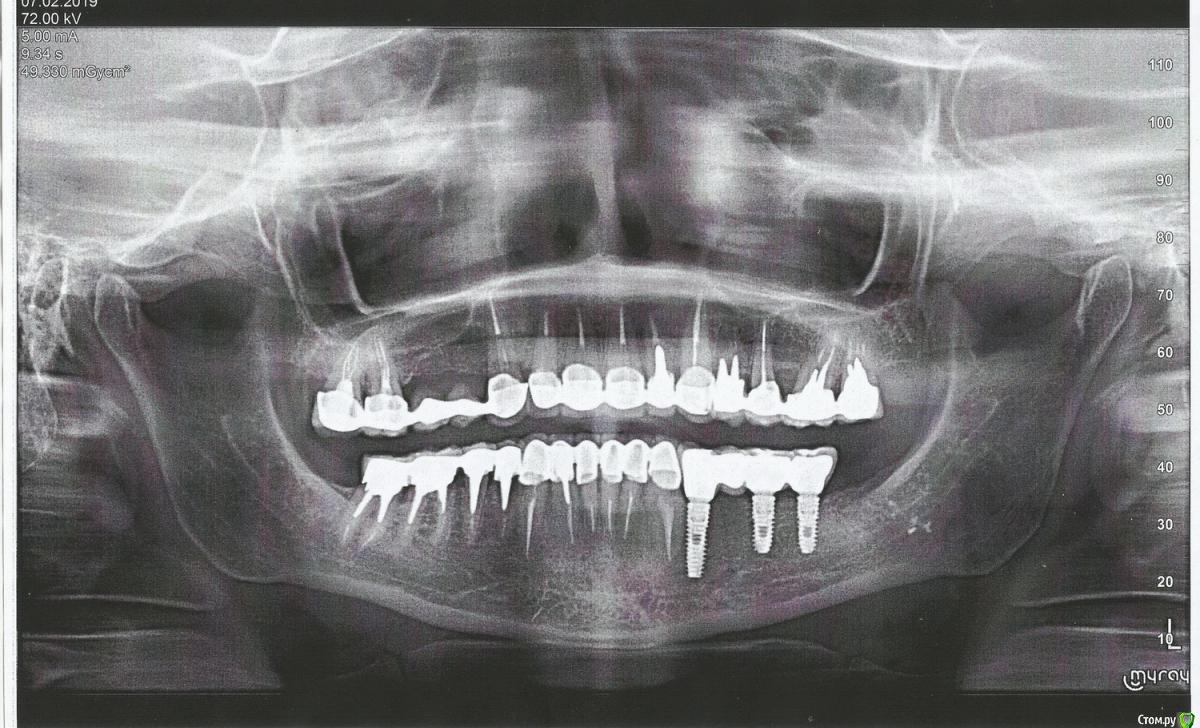

Ирина 0372 Опубликовано 7 февраля, 2019 Автор Поделиться Опубликовано 7 февраля, 2019 Покажите панорамный снимокВот, сегодня сделала: Ссылка на комментарий

DmitrySH Опубликовано 7 февраля, 2019 Поделиться Опубликовано 7 февраля, 2019 Здравствуйте, с лечением в целом все хорошо. Имплантацию справа почему решили не делать? Ссылка на комментарий

Ирина 0372 Опубликовано 7 февраля, 2019 Автор Поделиться Опубликовано 7 февраля, 2019 (изменено) Здравствуйте, с лечением в целом все хорошо. Имплантацию справа почему решили не делать?Спасибо Вам за ответ. Имплантирование вообще не планировала, но лет через пять после установки протезов, вспухла десна слева. После похода к доктору, выяснилось, что мне забыли поставить вкладку в тот зуб, возле которого появилась вздутие, из-за этого появилась киста. Пришлось удалить три зуба и поставить имплантанты. Скорее всего, со временем, придётся и справа ставить импланты.. Но наверно ещё можно так походить? Как Вы думаете, могу я заменить мост на пять зубов сверху, на отдельные коронки? Кроме желания, есть ещё и проблемка: на одном ( левом центральном зубе, я не знаю нумерацию по-правильному)), появилась трещина.. Кстати, как правильнее: импланты или имплантанты? Изменено 7 февраля, 2019 пользователем Ирина 0372 Ссылка на комментарий

DmitrySH Опубликовано 7 февраля, 2019 Поделиться Опубликовано 7 февраля, 2019 Кроме желания, есть ещё и проблемка: на одном ( левом центральном зубе, я не знаю нумерацию по-правильному)), появилась трещина.. Если речь про трещину корня, то стоматология не умеет лечить трещины. Такие зубы подлежат удалению и имплантации. соответственно коронки снимаются, делается временное протезирование, проблемный зуб удаляется, ставится имплант и потом коронки по отдельности. Ссылка на комментарий

Ирина 0372 Опубликовано 7 февраля, 2019 Автор Поделиться Опубликовано 7 февраля, 2019 (изменено) Если речь про трещину корня, то стоматология не умеет лечить трещины. Такие зубы подлежат удалению и имплантации. соответственно коронки снимаются, делается временное протезирование, проблемный зуб удаляется, ставится имплант и потом коронки по отдельности.Если речь про трещину корня, то стоматология не умеет лечить трещины. Такие зубы подлежат удалению и имплантации. соответственно коронки снимаются, делается временное протезирование, проблемный зуб удаляется, ставится имплант и потом коронки по отдельности. Нет, речь о трещине на самой коронке. Вы же не увидели трещин на каком-нибудь корне на снимке.. Речь о том, что хочу поменять мост на передних верхних зубах на отдельные коронки из диоксида циркония. Вы ответили, что в целом всё в порядке, но не сказали возможно ли заменить мост? В моем случае это возможно? Изменено 7 февраля, 2019 пользователем Ирина 0372 Ссылка на комментарий

___49___ Опубликовано 7 февраля, 2019 Поделиться Опубликовано 7 февраля, 2019 (изменено) В моем случае это возможно? исходя из предоставленной Вами информации , установить отдельные коронки на верхних 4 резца технически возможно. Но есть прикус которого я не вижу (и еще пару моментов) требующие очной консультации , для более достоверного ответа . Изменено 7 февраля, 2019 пользователем ___49___ 2 Ссылка на комментарий

DmitrySH Опубликовано 7 февраля, 2019 Поделиться Опубликовано 7 февраля, 2019 Нет, речь о трещине на самой коронке. это не страшно. Подумал что вы про корень зуба. В моем случае это возможно? Да, возможно. Но как правильно подметил коллега, есть нюансы которые надо оценивать очно 2 Ссылка на комментарий

DmitrySH Опубликовано 13 февраля, 2019 Поделиться Опубликовано 13 февраля, 2019 На самом деле с выбором метода изготовления коронок правильнее определяться после снятия ваших. ЕМАХ - эстетичнее на зубах с естественным цветом культевой части. Но у вас на зубе 22 стоит обширная культевая вкладка, которая может создать сложности с цветом коронки. Метод нанесения, что это за метод? Могли бы немножко подробнее рассказать? У меня еще есть время для определиться.. Обычно передние зубы всегда с нанесением, независимо от материала колпачка 3 Ссылка на комментарий